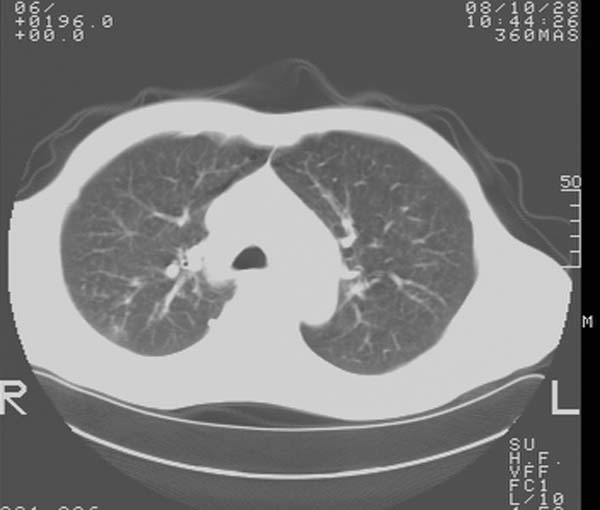

m,65y。半年前发现颈小结节,逐渐增多增大,现双侧耳后、颌下及颈部表浅淋巴肿大。胸片示双肺门增大。外院曾穿刺诊断为淋巴结核。在我科作胸腹部ct,我们觉得外院病检有误。现将图像上传请战友讨论。

纵隔内及腹膜后广泛淋巴结肿大,脾大,肝内似可见低密度影,结合病史半年前发现颈小结节,逐渐增多增大,现双侧耳后、颌下及颈部表浅淋巴肿大。考虑淋巴瘤。

纵隔,双肺门腹膜后多发淋巴结重大,非融合,肝脾轻度肿大,双肺野弥漫性小结节;考虑淋巴瘤,结节病可能性

纵隔内,双肺门、腋窝及腹膜后多发肿大淋巴结影,肺内小结节影,肝脾体积增大,支持淋巴瘤。肝内多发低密度影,考虑小囊肿。